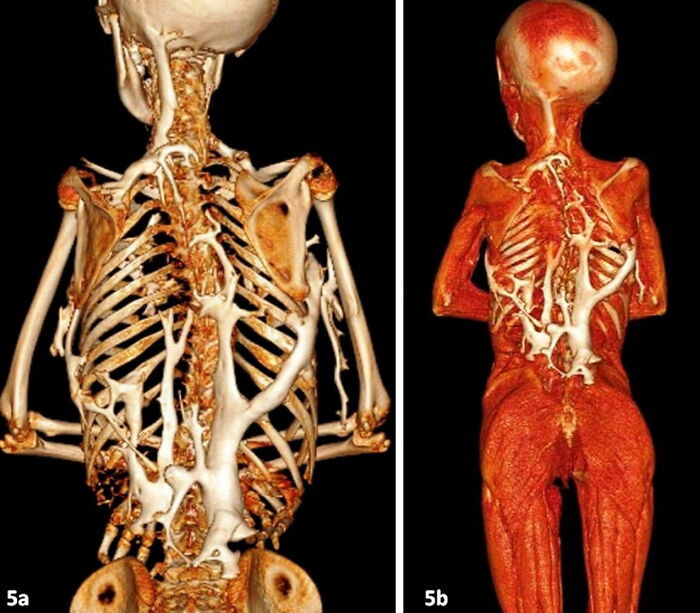

The Stone Man Disease: Fibrodysplasia Ossificans Progressiva